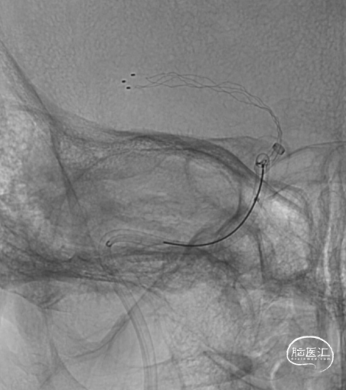

输送赛诺神畅 Ghunter™颅内取栓支架 ISR4-30到位,支架打开后造影可见血栓位于颈内动脉末端至大脑中动脉M1段。

第一次支架取栓,无明显血栓取出,造影可见颈动脉仍闭塞。

微导管再次通过闭塞段,造影可见颈内动脉末端及大脑中动脉、大脑前动脉通畅。考虑血栓向近心端移动。

再次释放赛诺神畅 Ghunter™颅内取栓支架 ISR4-30,支架释放过程流畅。

赛诺神畅 Ghunter™颅内取栓支架 ISR4-30全程显影清晰,可见颈内动脉末端支架被血栓压迫。

第二次支架取栓,右大块血栓取出,造影可见颈动脉动脉再通,右侧大脑中动脉、双侧大脑前动脉显影可,颈内动脉C1段痉挛。